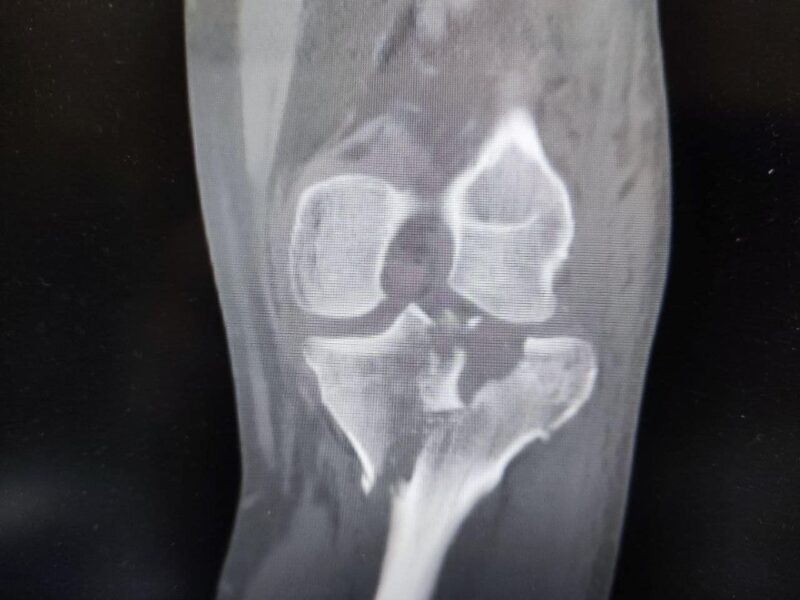

«ДТП сталася на початку вересня. 35-річний Мирослав Петрилко їхав на мотоциклі та зіткнувся з легковою автівкою. Після падіння мотоцикліст зрозумів, що його ліва нога зовсім не рухається. Карета швидкої доправила постраждалого до нашої лікарні. Після обстеження медики діагностували у Мирослава закритий багатофрагментарний внутрішньосуглобовий перелом обох виростків лівої великогомілкової кістки», – йдеться у повідомленні.

«Це є найскладніший по класифікації внутрішньосуглобовий перелом гомілки в ділянці колінного суглобу. Аби уникнути інвалідизації пацієнта та в подальшому відновити функцію травмованої кінцівки, необхідне реконструктивне операційне втручання з використанням титанових конструкцій та кісткових трансплантатів», — розповідає Юрій Кіт, ортопед-травматолог Лікарні Святого Луки Першого медоб’єднання Львова.

Під час операції медики спершу виконали репозицію кісткових уламків колінного суглобу, тобто повернули їх у правильне анатомічне положення. Потому замістили кістковий дефект штучним трансплантатом. І вже останнім етапом ортопеди-травматологи … зафіксували суглоб титановими пластинами.